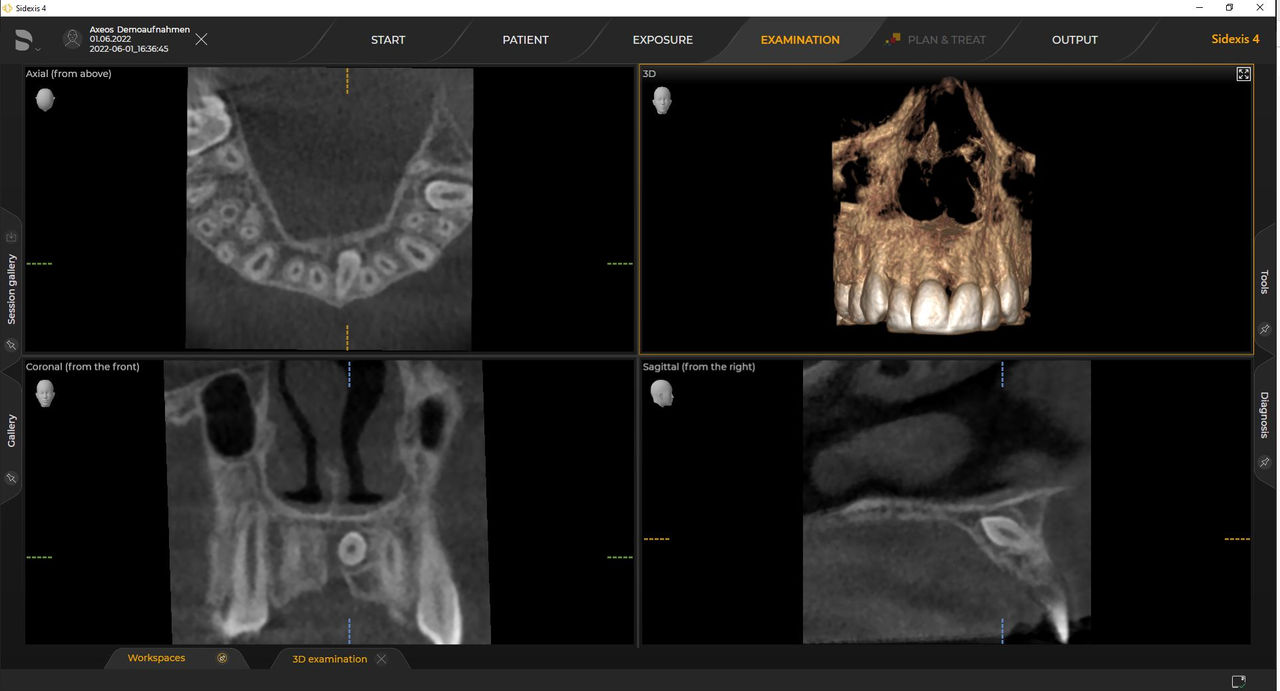

Das 2D-/3D-System mit großem Volumen und hoher Bildqualität für Praxen mit breitem Behandlungsspektrum. Gemeinsam mit Zahnärzten und Behandlern entwickelt, bietet Axeos von allen Dentsply Sirona Extraoral-Röntgengeräten das breiteste Behandlungsspektrum. Neben einer exzellenten Bildqualität und maßgeschneiderten 3D-Volumengrößen zeichnet sich das Röntgengerät durch einen hohen Patientenkomfort aus. Axeos bietet nicht nur Qualität bei Leistung und Komfort, sondern überzeugt auch durch sein preisgekröntes Design mit einem integrierten Aufbiss-Ordnungssystem und Ambient Light

Zahlreiche Volumengrößen sorgen für Flexibilität im Praxisalltag. Untersuchung eines bestimmten Bereichs oder Beurteilung der gesamten Bezahnung einschließlich der Kiefergelenke.

Mit dem Intelligent Low Dose-Modus erhalten Sie 3D-Bilder im Dosisbereich einer 2D-Röntgenaufnahme. Im HD-Modus werden während eines einzelnen Umlaufs bis zu 1.400 Einzelbilder aufgenommen und zu einem 3D-Volumen mit bis zu 80 μm zusammengeführt. Der Vorteil für Sie: rauschärmere Aufnahmen in hoher Auflösung.

Dentsply Sirona 3D-Röntgengeräte arbeiten exklusiv mit Sidexis 4 zusammen. Aber die Datenmigration von Sidexis XG zu Sidexis 4 ist sehr einfach. Wir empfehlen den Wechsel zu Sidexis 4, um die vollen Vorteile des digitalen Prozesses mit den neuesten Werkzeugen zu erleben.